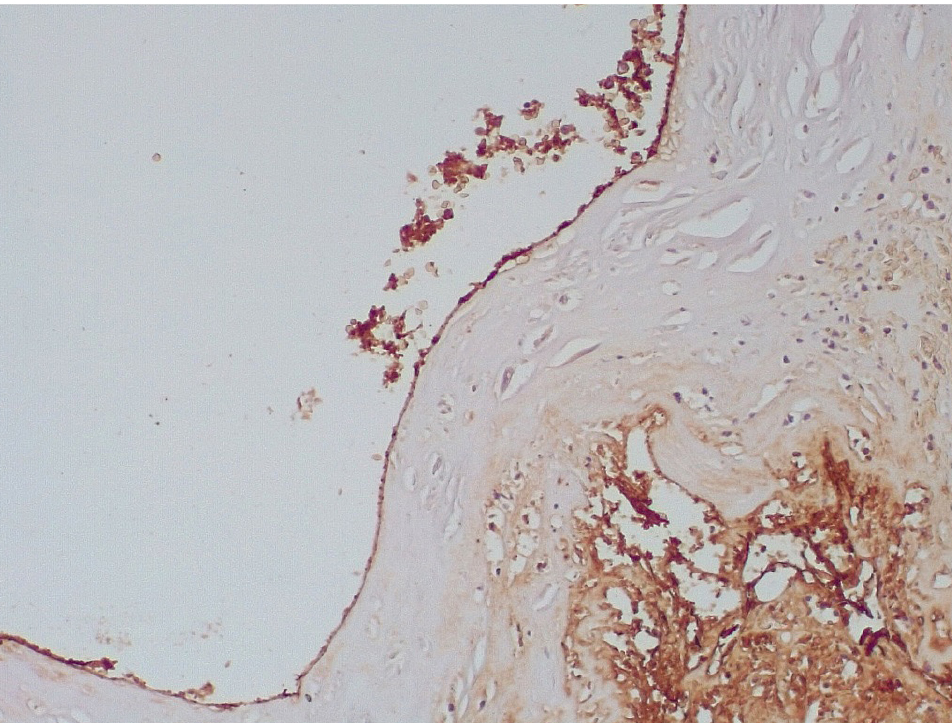

Обращало внимание, что в местах «оголенного» эндотелия КА отмечалась слабая экспрессия белка CD31, что указывало на выраженные дистрофические и некробиотические изменения клеток (рис. 2). При этом экспрессия ФВ была яркой, выраженной на всем протяжении интимы КА (рис. 3).

Маркер эндотелиальной дисфункции – фактор Виллебранда (ФВ) ярко экспрессировался в клетках эндотелия КА и субинтимально, что могло свидетельствовать о выраженной дисрегуляции коагуляционных свойств крови (рис. 5). В то же время экспрессия белка CD31 в указанные сроки после стентирования была слабовыраженной, что могло указывать на выраженные дистрофические изменения эндотелиальных клеток КА.

Сохранялась резковыраженная яркая экспрессия ФВ как со стороны интимы, так и субинтимально, в участках альтерации атером (рис. 8). В то же время экспрессия белка CD31 была негативной на всем протяжении стенок КА.

Наиболее значимым маркером эндотелиальной дисфункции, отражающим нарушение коагуляционных свойств крови, является белок фактор Виллебранда, экспрессия которого была резко выраженной во всех группах умерших после стентирования КА.